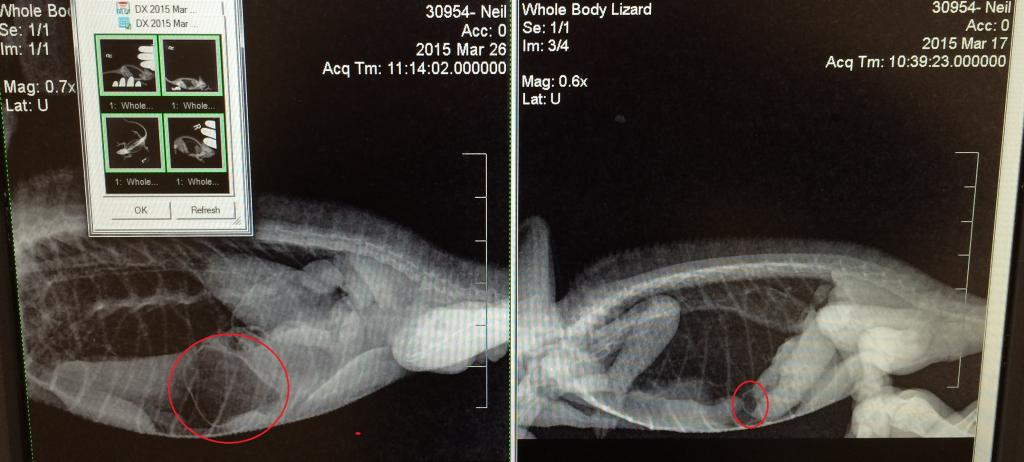

X-RAY: Right image is from 3/17. You can see the urate quite easily. I circled what the vet thought was a blockage.

Left image is from yesterday. What we thought was a blockage has enlarged. The vet thought maybe it was gas, but again, hard to tell. Our vet is knowledgeable in chams and came highly recommended.